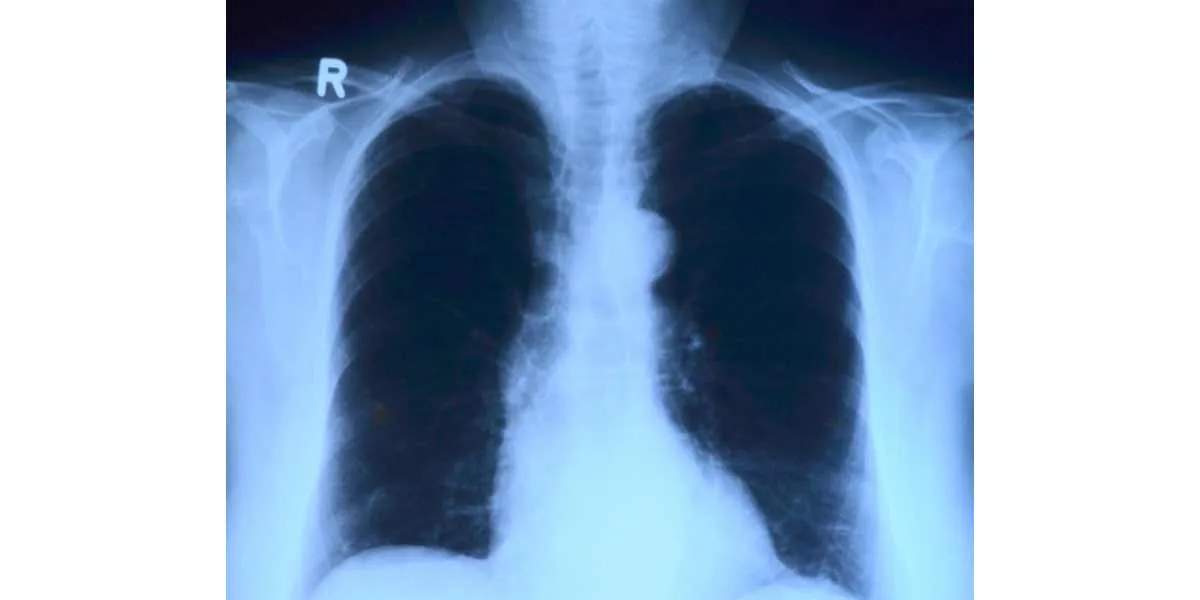

A lo largo de la carrera, a todos los estudiantes de Medicina nos han hablado de lo importante que es saber interpretar correctamente una radiografía de tórax. Las placas de tórax se piden en prácticamente cualquier especialidad, incluso como estudio básico junto al análisis de sangre, por eso, es de vital importancia tener unos conceptos básicos de lectura que nos permitirán interpretar con facilidad cualquier radiografía que caiga en nuestras manos (incluso como estudiantes).

En primer lugar, antes de meternos a leer cualquier tipo de información clínica, debemos cerciorarnos de que la radiografía esté “bien hecha”: es decir, paciente bien colocado, en inspiración, centrada, con correcta penetración, y visualización de campos. Los datos técnicos son el punto de partida.

– Para comenzar la lectura clínica, lo ideal es empezar con una impresión global de la radiografía, es decir, echar un vistazo general y en conjunto a la placa, sin pararse a precisar detalles particulares. Nos iremos quedando con los datos de simetría, forma, tamaño, sexo del paciente, edad, etc …o con cualquier dato que salte a la vista y nos llame la atención (por ejemplo, un marcapasos).

Echaremos un vistazo a las vías respiratorias (la tráqueaopens in new tab/window, la carina y la división de los bronquiosopens in new tab/windowprincipales). Tras llevar a cabo una visualización global de los pulmones (descartando alteraciones de la densidad, del patrón vascular y del parénquimaopens in new tab/window), nos fijaremos primero en la zona apical, por encima de las clavículas, comprobando asimetrías. Después, valoraremos la zona zona hiliar, su tamaño, situación y morfología (vascular). Descartaremos masas, adenopatíasopens in new tab/window y aumento del tamaño de los vasos. Identificar los distintos lóbulos y cisuras pulmonares, tanto en la proyección AP como en la lateral.

– Para valorar la silueta cardíaca y los vasos, la radiografía se realizará en bipedestación y en inspiración forzada, ya que en decúbito y en espiración la silueta cardíaca puede parecer aumentada. Tendremos que fijarnos en el tamaño del corazón en general y sus cavidades por separado, descartando una posible cardiomegaliaopens in new tab/window.

El índice cardiotorácico (ICT) se calcula midiendo (en la proyección PA) desde la punta más distal izquierda (ápex) hasta la parte más externa de la sombra cardiaca derecha y se divide entre el diámetro torácico (distancia entre ambas costillas internas a nivel de la cúpula diafragmática derecha). Se considera un aumento de la silueta cardiaca si el índice cardiotorácico es mayor de 0,50.